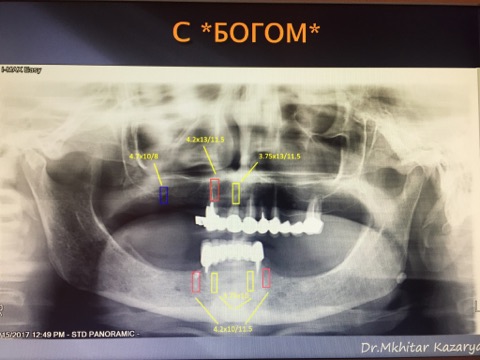

Мастер-класс начался с обсуждения предстоящей операции и снимка компьютерной томографии, после чего участники смогли присутствовать на операции.